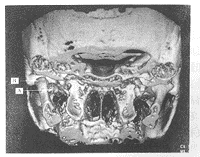

14例患者中,发现单、双侧髁突骨折各7例,共21侧。其中髁突高位骨折18侧,颈部骨折3侧。高位骨折中,关节面以下的斜行骨折11侧,经过关节面的纵行骨折3侧,粉碎性骨折4侧。3侧颈部骨折全部为内弯骨折(1侧为青枝骨折)。高位斜行骨折和粉碎性骨折髁突移位较大,大多向前下内移位,常伴有旋转(图1)。而纵行骨折移位较小(图2)。颈部内弯骨折髁突向内旋转移位(图3)。本组中10例15侧行手术复位,手术所见与三维重建影像完全一致。在已行颌间牵引复位的病例,未观察到移位的髁突有复位迹象。

图1 左髁突关节面以下斜行骨折(后前位)

A 髁突前下内方移位, B 下颌升支上移骨折断面与关节窝接触